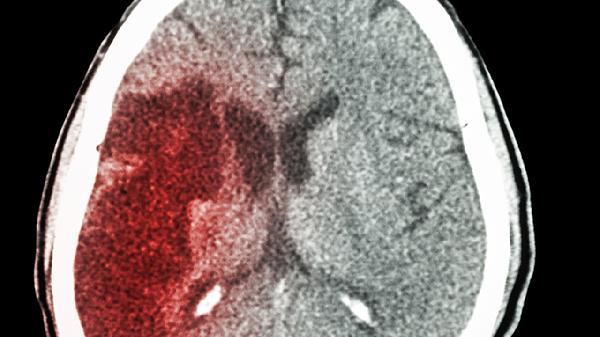

二次中风伴脑出血需立即就医,治疗方式主要有控制血压、降低颅内压、手术清除血肿、预防并发症、康复训练等。二次中风伴脑出血通常由高血压、动脉瘤破裂、脑血管畸形等因素引起,可能伴随头痛、呕吐、意识障碍等症状。

对于出血量较大或位于关键脑区的血肿,可能需手术干预。常见术式包括开颅血肿清除术、立体定向血肿穿刺引流术等。手术时机和方式需根据患者具体情况决定。术后需密切观察神经功能变化,预防感染等并发症。

二次中风伴脑出血患者需长期随访,定期复查头部CT或MRI评估恢复情况。日常生活中应严格遵医嘱服药,控制血压、血糖、血脂等危险因素。饮食宜清淡,限制钠盐摄入,适当补充优质蛋白和膳食纤维。避免情绪激动和剧烈运动,戒烟限酒。家属需学习基本护理知识,密切观察患者病情变化,发现异常及时就医。